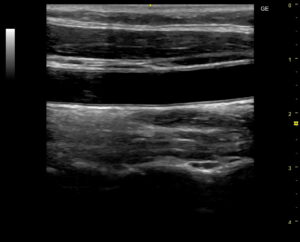

頸動脈は、首の左右を通って脳に血液を送る太い血管です。この頸動脈の壁の厚さや血流を超音波で観察し、動脈硬化の進行度や血管の状態を確認するのが頸動脈エコー検査です。

- 血管壁の厚さ(IMT:内中膜複合体厚) – 厚みが増すと動脈硬化が進んでいるサイン

- プラーク(血管内の脂肪沈着) – 脳梗塞や心筋梗塞の直接原因となることも

- 血流の速度・乱れ – 狭窄や閉塞の有無を確認

- 専用のジェルを塗り、超音波プローブを当てて観察します。

- 画像を解析し、血管壁の厚みやプラークの有無を評価します。

痛みはなく、リラックスして受けられます。結果は画像で確認でき、血管の“老化度”を視覚的に理解できます。